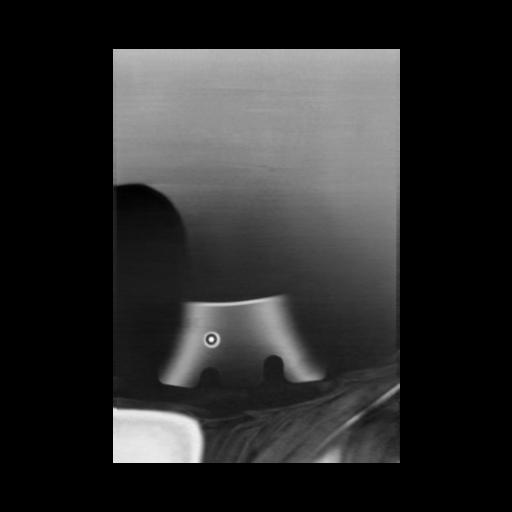

13 P.BLANDAS,,Coronal,2.000,P.BLANDAS,Coronal,